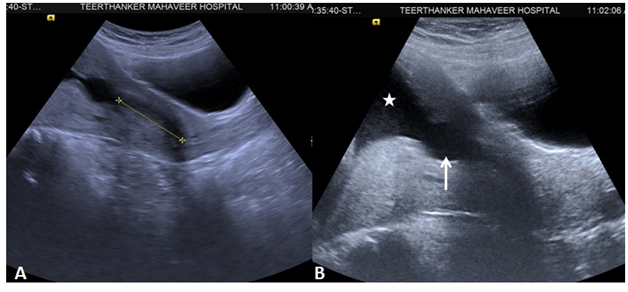

Cervical elastography

Elastography is an USG based imaging technique for assessment of the consistency of the cervical tissue/internal os. It is method of virtual palpation based on the concept of greater compression of the softer tissue on pressure as compared to the harder tissue. The gradient of the strain produced is displayed on color coded and a gray scale map. eSie Touch EI method is provided in Acuson S2000 USG (Siemens Healthcare, Erlangen, Germany) system which generates both gray scale and color coded maps across the soft to hard tissue consistency without application of pressure on the cervix. Most of the studies done previously have stressed on the assessment of the color coding of the region of the internal os.11‒13 Thomas et al.14 has mentioned the grading based on the color map,14 with red indicating soft, yellow (medium soft), green (medium hard) and blue or purple (hard). The grading was done on proportion of the colors on the color map. However, the cervical softening and prediction of the preterm is primarily based on red to yellow colors.11 Cervical elastography is done in the second trimester of gestation on patients presenting with clinical signs and symptoms of preterm labor and preterm premature rupture of membranes (PPROM) for the morphological assessment of the cervix. However, this Real Time Elastography (RTE) method is subjected to inter as well as intra observer variation; hence lacks standardization. Bishop’s scoring, cervical length and RTE of the cervix can be correlated for the assessment of the risk of preterm birth (Figure 3).

Figure 3 Shear wave elastography of the cervix. (A) Shear wave velocity is reduced indicating soft cervix. (B) increased velocity indicating the hard cervix.

Another recent advancement in the elastographic technique is based on Acoustic Radiation Force Impulse (ARFI) which is a quantitative method for measuring the velocity of the shear waves from the tissue concerned. The technique is better known as Virtual Touch tissue Quantification (VTQ). In this model, the region of interest (ROI) is placed at the concerned site (internal os in this scenario) and the velocity is measured as m/sec.

ARFI ultrasound imaging is currently used for evaluation of tissue elasticity in the liver, pancreas, breast, thyroid and prostate.15,16 The technique is previously utilized in the cases of cervical malignancy17 and there is reasonable dearth of the literature regarding its role in assessment of preterm birth. The ROI box measures 6x10mm with tissue within 80mm depth from the skin surface. Hence, some of the cases with deeper internal os and some with motion artifacts needs to excluded. The study can be extended for standardization of the elastography based on quantified results and lack of observer variability. Hence an average VTQ value in m/sec can be defined for the soft and hard cervix.